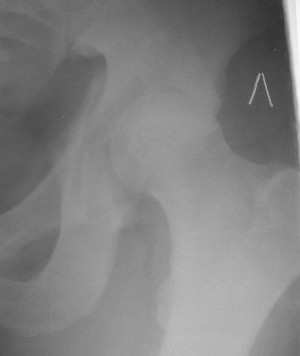

Больной 18 мая 2003 года в автоаварии получил перелом левой вертлужной впадины, вывих бедра. Госпитализирован в один из стационаров области.Вывих вправлен. В последствии бедро вывихивалось еще дважды. На консультацию был представлен снимок от 19.05.03г., больной переведен к нам 3.06.03г. Снимок при поступлении - перелом впадины, задне-верхний вывих бедра. 05.06.2003 г. выполнено открытое вправление вывиха левого бедра и остеосинтез стенки вертлужной впадины двумя винтами. Послеоперационный период без осложнений. Объем движений в левом тазобедренном суставе восстановился полностью. Выписан на амбулаторное лечение в удовлетворительном состоянии с рекомендациями 3 месяца ходить на костылях без нагрузки на оперированную конечность. На контрольных рентгенограммах левого тазобедренного сустава 13.10.2003 г. - признаки консолидации перелома; плотность, форма головки и состояние суставных поверхностей удовлетворительные. Разрешена дозированная осевая нагрузка, на конечность с использованием дополнительной опоры. 19.12.2003 г. больной обратился с жалобами на боли в левом тазобедренном суставе. На рентгенограммах левого тазобедренного сустава 19.12.2003 г., 20.02.04г. - асептичекий некроз головки бедра. 5.04.04г. - эндопротез. Сейчас ходит без трости, не хромает. Особенность эндопротезирования - при удалении винтов прослежена линия перелома заднего края впадины и предложено установить чашку несколько меньшего диаметра, чтобы она была покрыта несломанной частью.

Случай, представленный Вами, совсем не идентичен обсуждаемому. У Вашего пациента был поперечный перелом с переломом заднего края, а в обсуждаемом случае - высокий двухколонный перелом вертлужной впадины.

То есть в представленном Вами случае был перелом заднего типа, в нашем случае центрального. У Вашего больного был застарелый задний вывих, у нашего - перелом шейки. Столь раннее разрушение головки, вероятно, было во многом обусловлено тем, что не была достигнута анатомическая репозиция, головка бедра осталась смещенной кзади, что является частой ошибкой при крупных фрагментах свода.

Необходимость фиксации вертлужной впадины в нашем случае вообще под вопросом, так как конгруэнтность сохранена (вторичная конгруэнтность типична для двухколонных переломов).